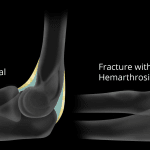

- Acute mildly displaced supracondylar fracture with posterior angulation

- Elbow joint effusion

- Supracondylar humeral fracture

- Supracondylar humeral fractures are the most common elbow fractures in young children

- The usual mechanism for supracondylar fractures is hyperextension at the elbow resulting in the olecranon impacting on the posterior humerus. The resultant fracture often has posterior angulation or displacement